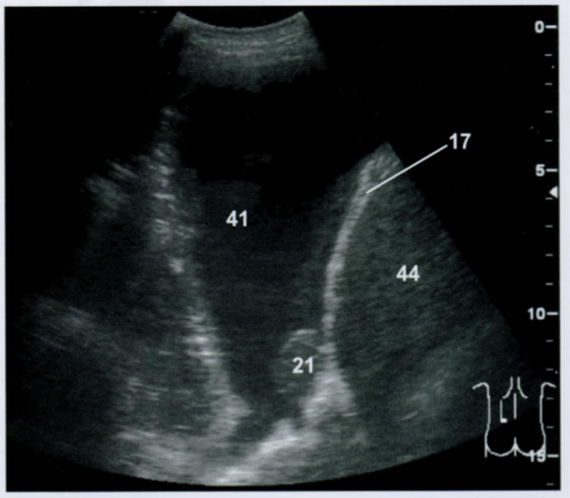

При ультразвуковой визуализации показаны плевральный метастаз (21) с сопутствующим выпотом (41) у пациента с раком легкого. Метастаз расположен с грудной стороны диафрагмы (17) на париетальной плевре над селезенкой (44).